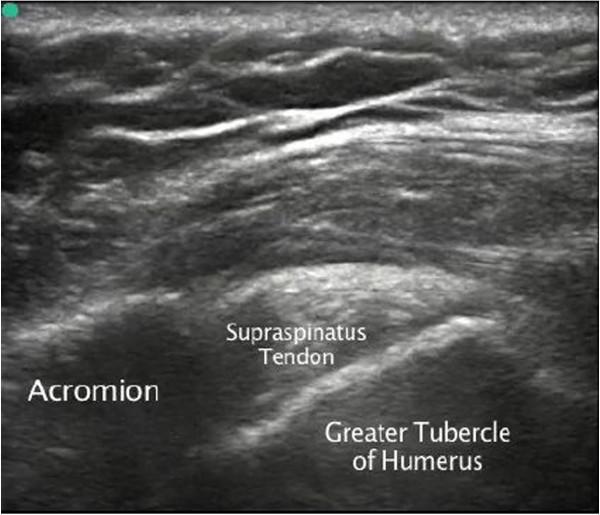

急诊科应用床旁超声诊断冈上肌腱钙化和肩峰撞击综合征

Emergency department diagnosis of supraspinatus tendon calcification and shoulder impingement syndrome using bedside ultrasonography.

A 45-year-old woman presented to the emergency department with a 2-day history of severe left shoulder pain made worse with movement. Emergency department (ED) bedside point-of-care static and dynamic ultrasound examination of the supraspinatus tendon revealed supraspinatus tendon calcification with impingement syndrome, and the patient was urgently referred to orthopedics after ED pain control was achieved. Bedside shoulder and supraspinatus tendon evaluation with static and dynamic ultrasonography can assist in the rapid diagnosis of supraspinatus tendon calcification and supraspinatus tendon impingement syndrome in the emergency department.

一名45岁女性因严重左肩疼痛2天前来急诊科就诊,活动时疼痛加剧。急诊科床边即时超声对冈上肌腱进行静态和动态检查,发现冈上肌腱钙化伴撞击综合征,在急诊科疼痛得到控制后,该患者被紧急转诊至骨科。床边使用静态和动态超声对肩部及冈上肌腱进行评估,有助于在急诊科快速诊断冈上肌腱钙化和冈上肌腱撞击综合征。